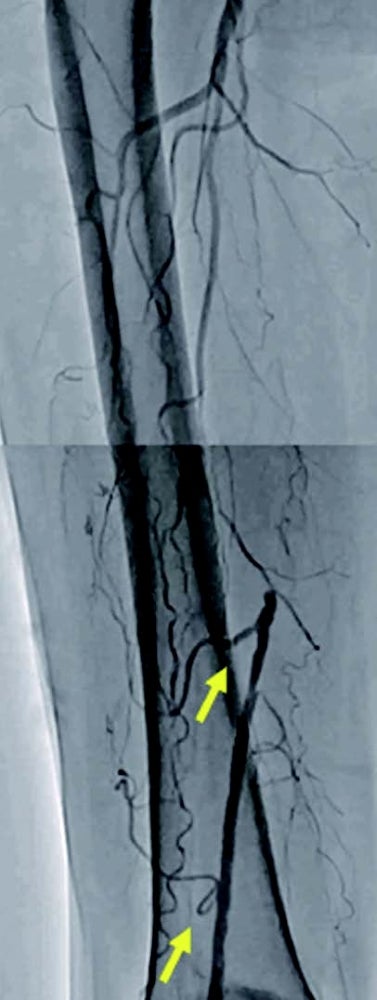

左浅大腿動脈閉塞(図1):右鼠径部を穿刺(6 Frシース)しcrossover後、順行性に0.014 inchマイクロカテーテルを使用して0.014 inchガイドワイヤー(先端荷重1 g→40 g)を進め貫通、IVUS catheterで真腔を捕らえていることを確認。5.0 mm径バルーン(non-compliant balloon)で拡張後解離が生じ、末梢にバイアバーン® ステントグラフト5.0 × 150 mm、中枢に6.0 × 150 mmの2本を留置。病変の末梢には発達した1本の側副血行路を伴い、側副血行路の中枢側に健常部位があったため、側副血行路をjailせずバイアバーン® ステントグラフトを留置。5.0 mm径と6.0 mm径バルーン(non-compliant balloon)で後拡張して終了。(図2)